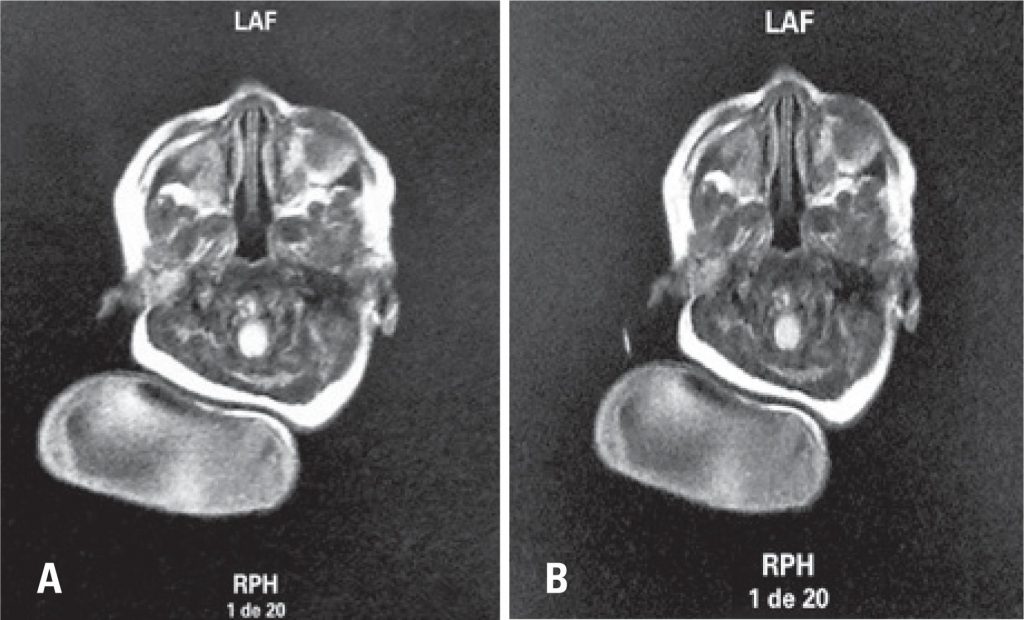

Congenital occipital myelocele

Congenital encephalocele is a neural tube closure defect that presents herniation of cranial contents because of a cranial congenital malformation, the occipital encephalocele is the most common form of this defect.() Encephalocele often occur because of occurrence of occipital bone defect within the fourth week of embryogenesis and it can be extended for foramen magnum and affect the posterior arch of the atlas.() Hernia sac content varies and worst prognosis is large brain content inside the sac.(,) Etiology of this malformation include genetic and environmental factors, such as folate deficiency that is prevented with the use of folic acid supplements during preconception period until 12 weeks of gestation, and also for poor prenatal care.(,) Although this malformation varies in several demographic regions, neural tube closure defects incidence is approximately 1 in 1,000 live births.(,)

Both adequate prenatal care and imaging tests are importance to identify variations of this affection. For this reason, clinical case reports and their on encephalocele images are important.